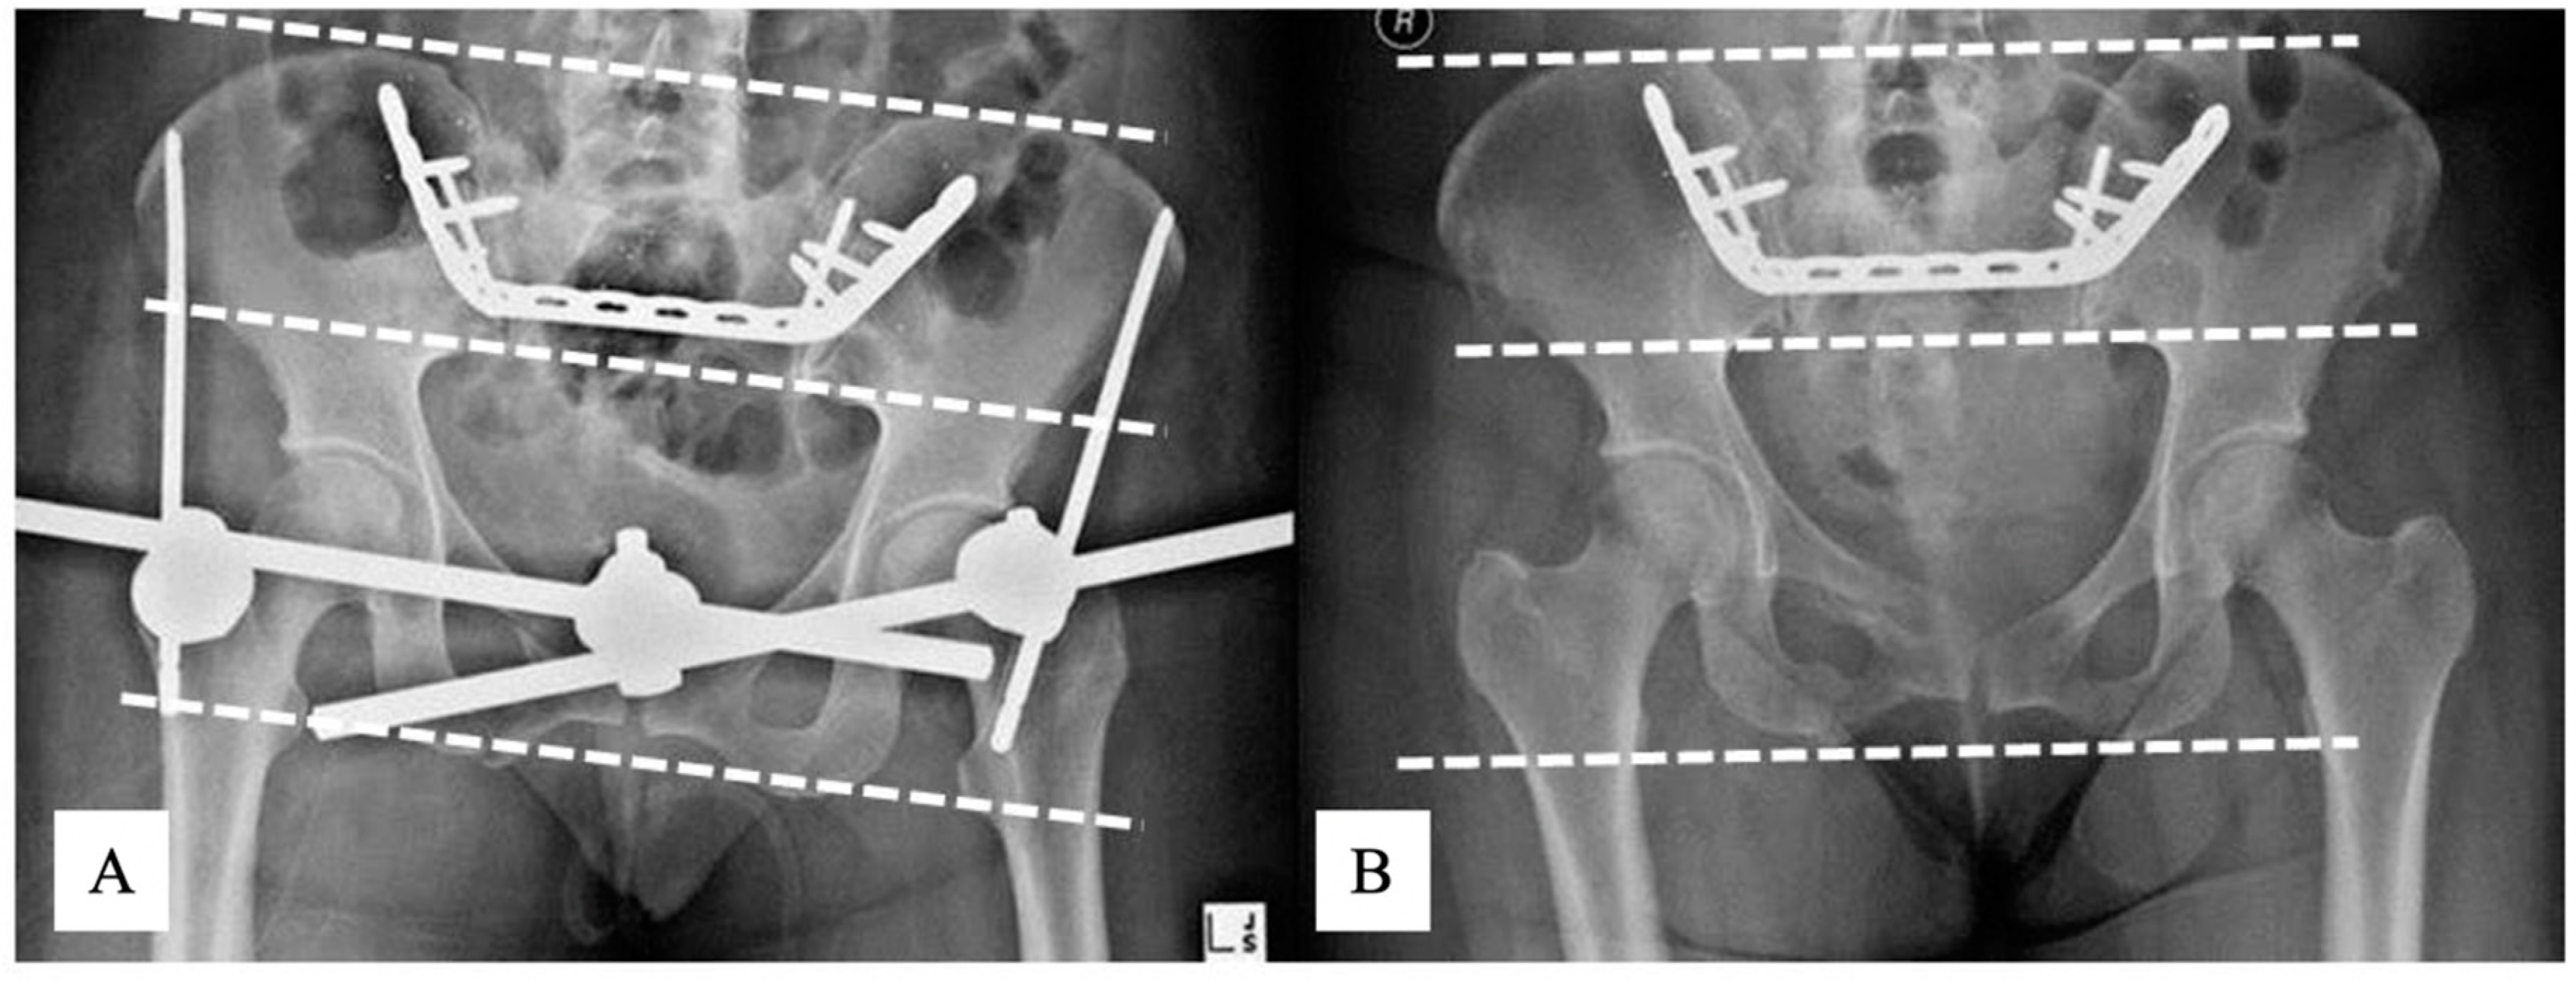

3.3. Radiographic Results

3.4. RSA

3.4.4. Pelvic Displacement Caused by the Removal of the External Fixator